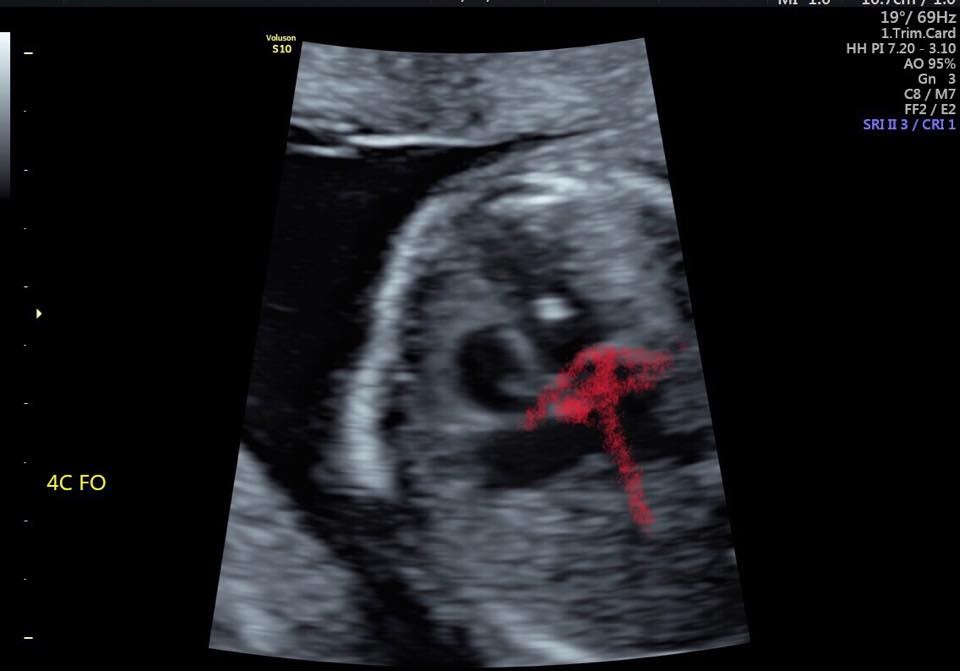

高層次超音波與染色體異常 Dr Chen 透視胎兒的世界 痞客邦